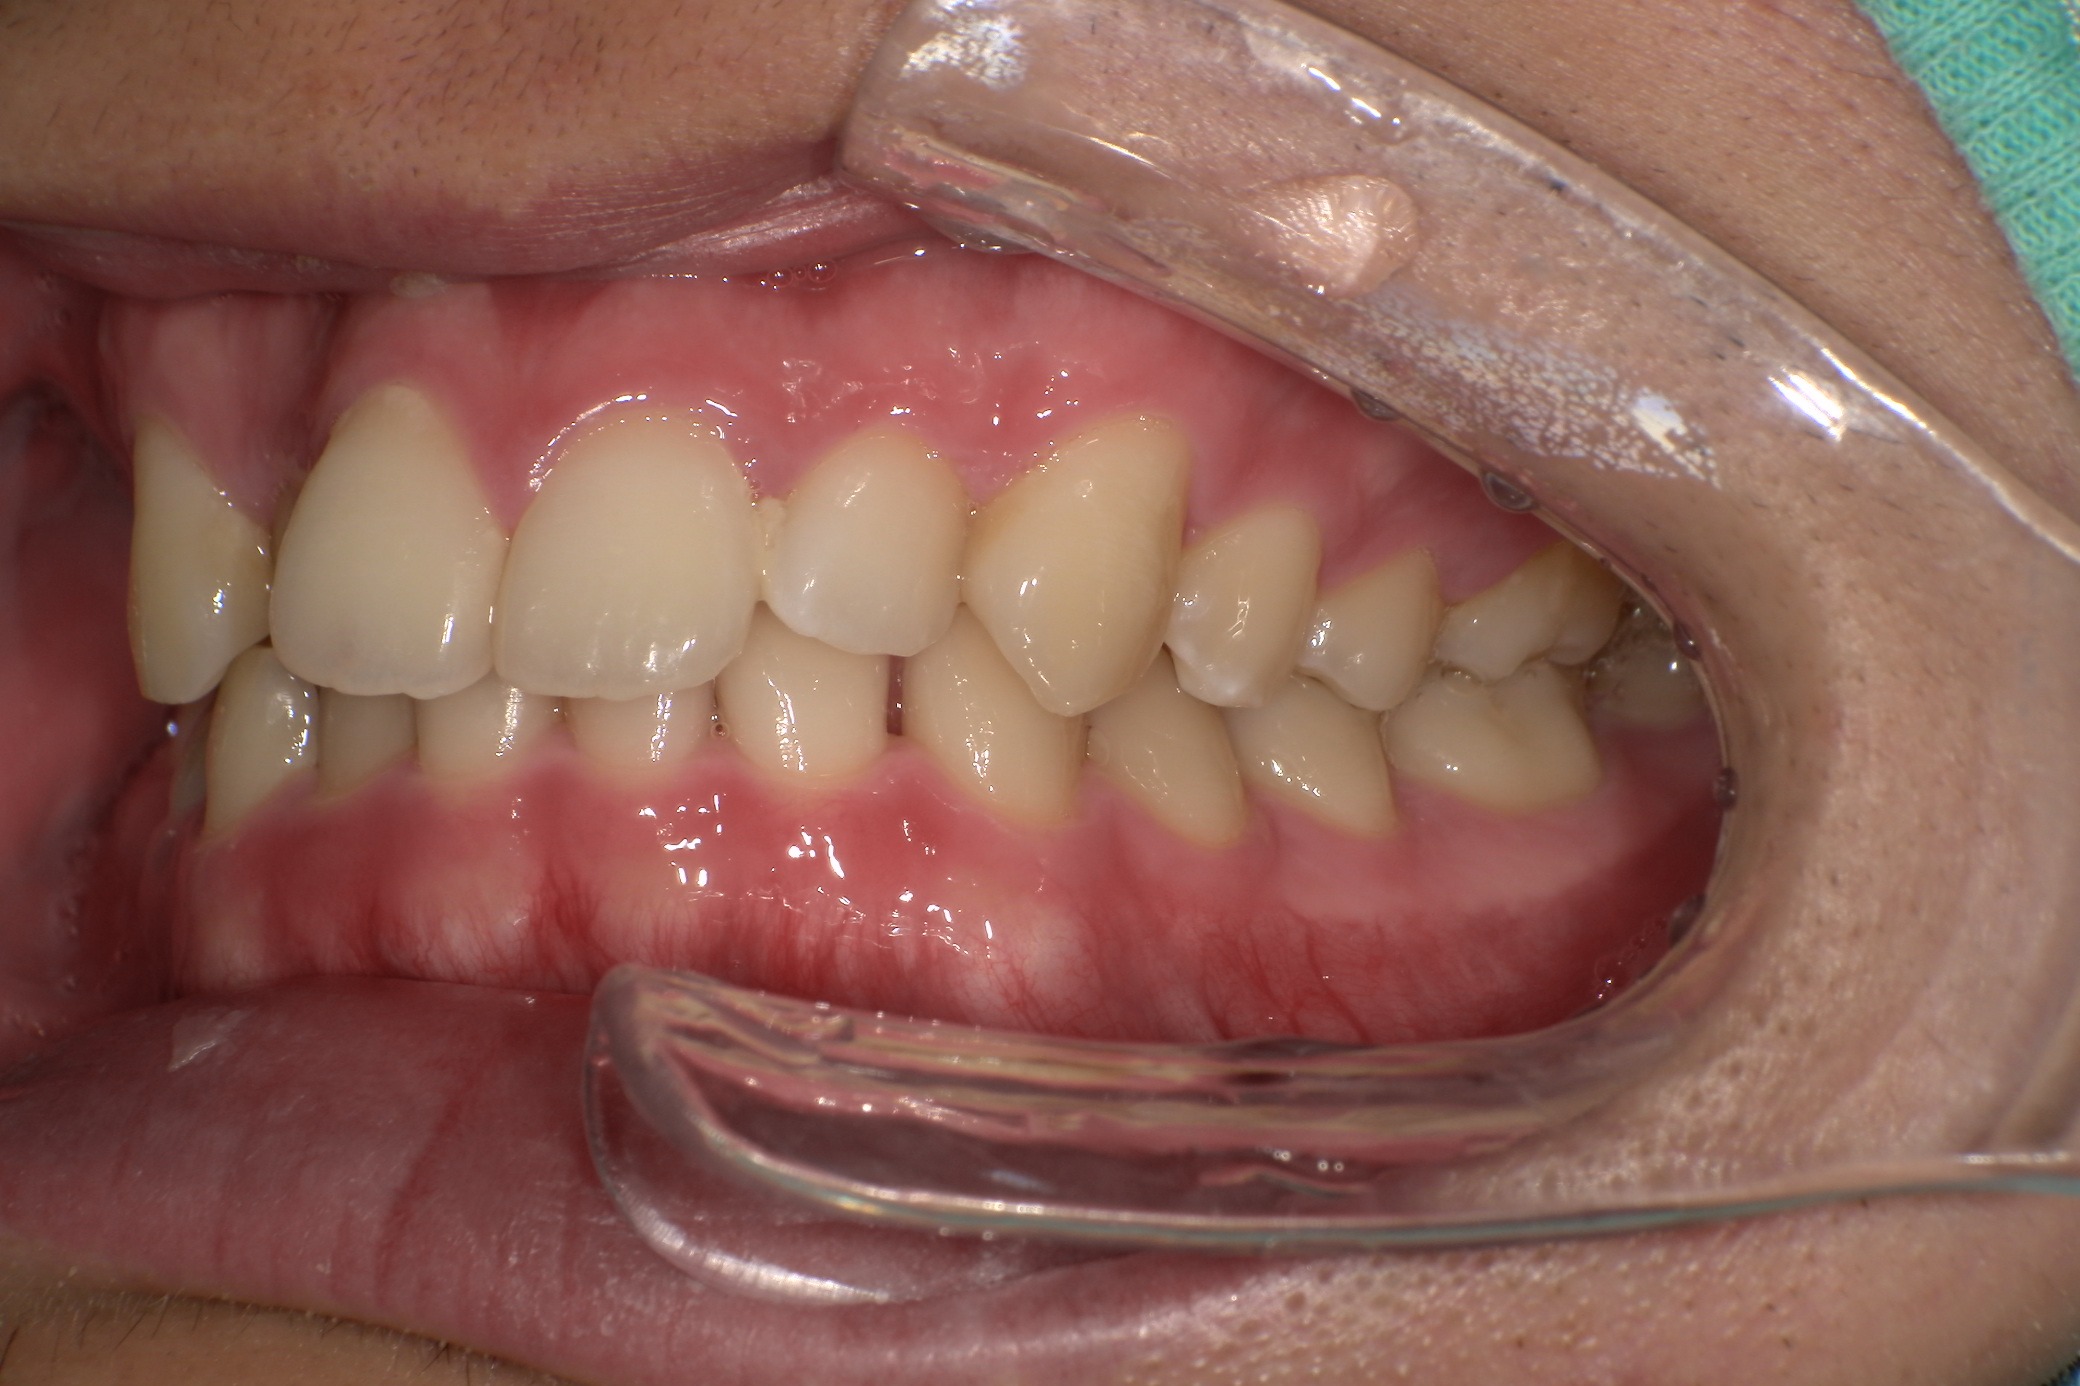

歯並びがコンプレックスで友人と写真を撮る際も気にしてしまっていたという20歳の男子大学生I.T.様にのI.T.様。始めやすい価格と目立ちにくさからスマイルモア矯正を選び、自信を持って笑えるようになった経緯を伺いました。

| 治療内容 | マウスピースを用いた歯列矯正 |

| 追加処置 | IPR |